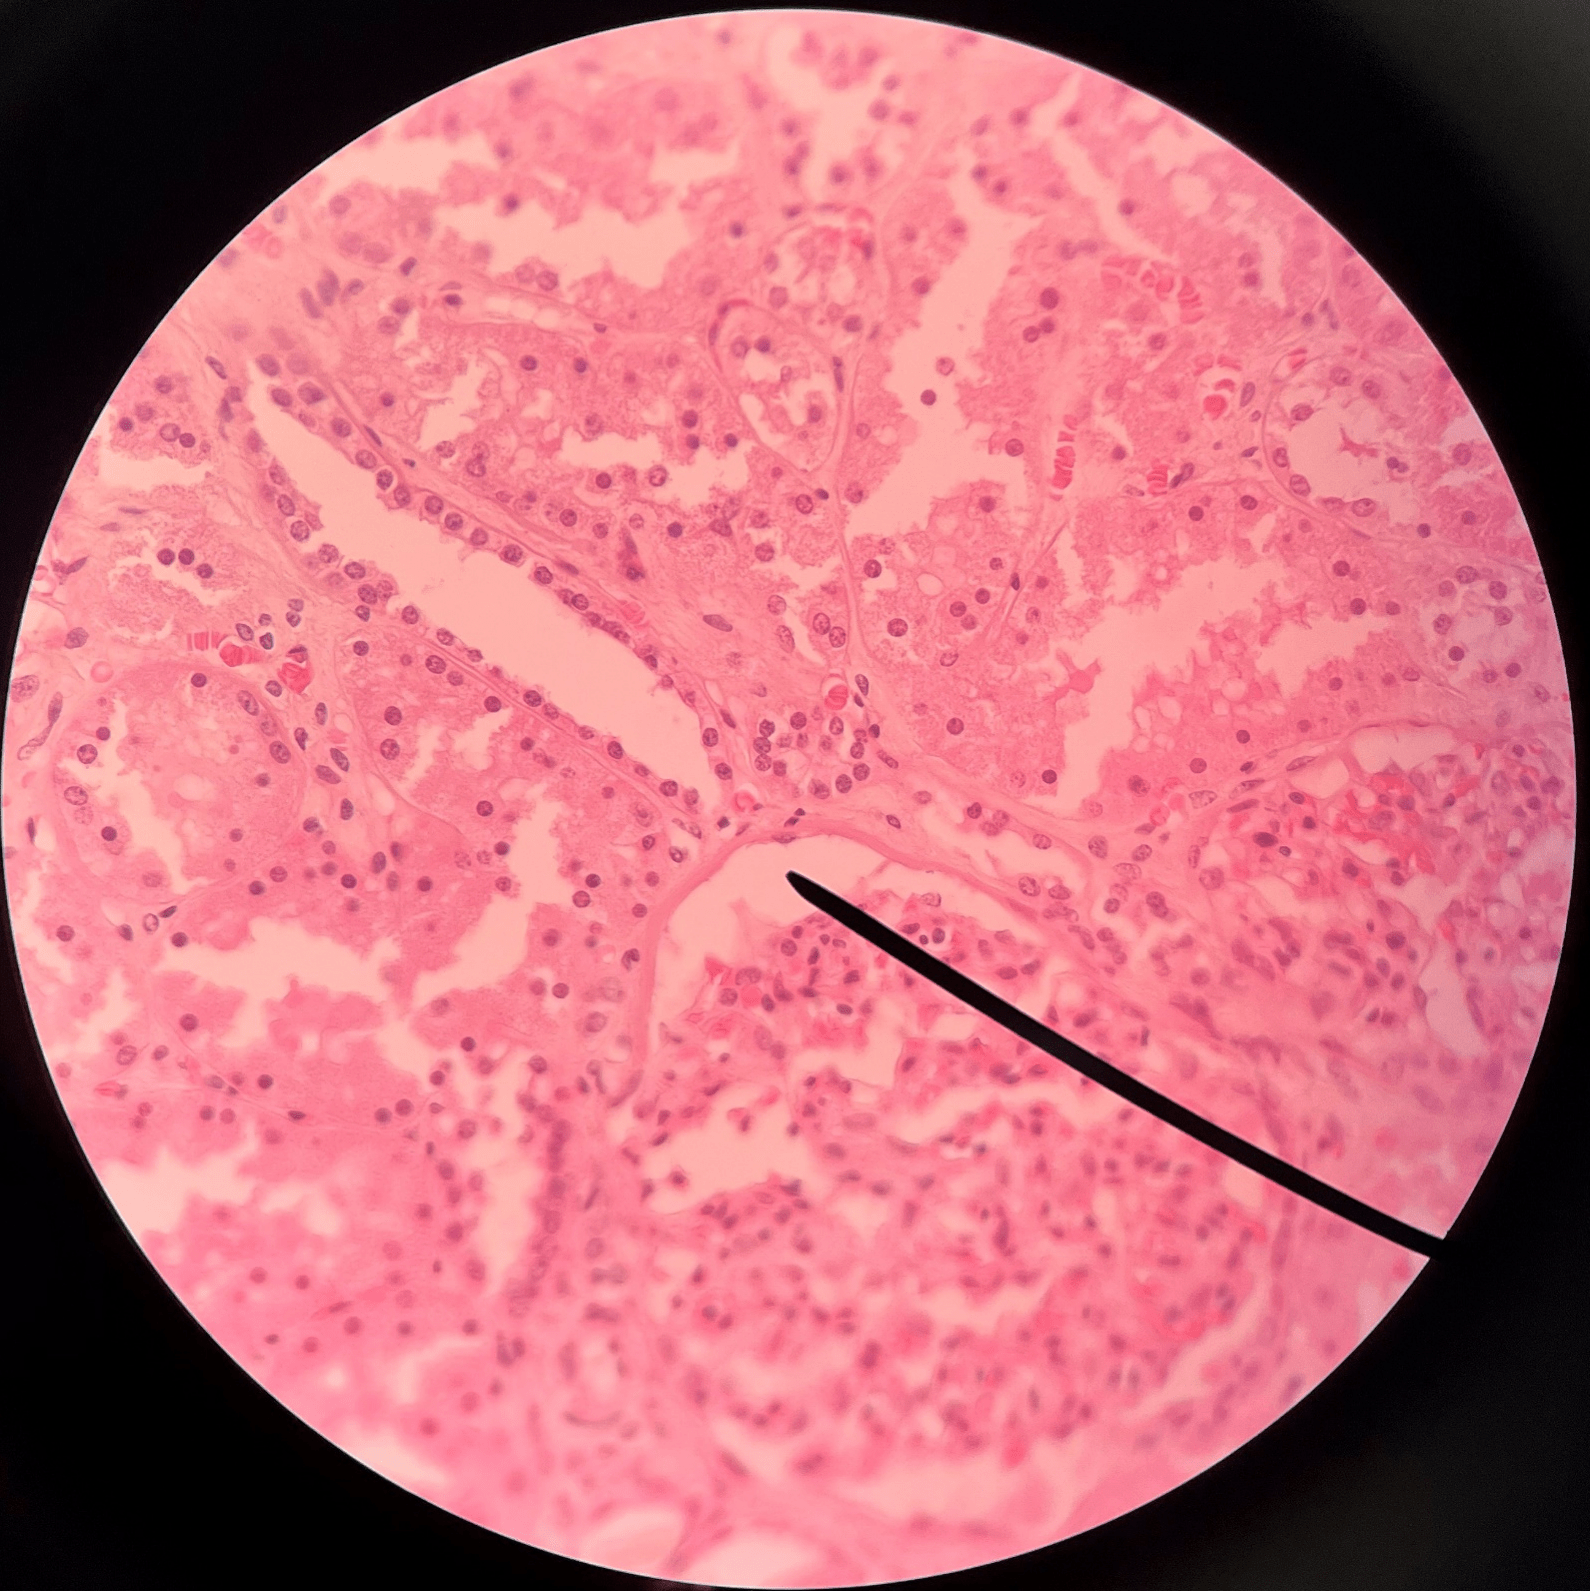

nephron

• The functional subunit of the kidney.

• Site of urine formation and renal function.

• Composed of a renal corpuscle and a renal tubule.

renal corpuscle

• Part of a nephron.

• Filters blood.

• Composed of a glomerulus enclosed within a glomerular capsule.

glomerulus

• Slide histology of the nephron.

• Part of a renal corpuscle.

• The capillary network of a renal corpuscle.

capsular space

• Slide histology of the nephron.

• Part of a renal corpuscle.

• The interior of the glomerular capsule.

glomerular capsule

• Slide histology of the nephron.

• Part of a renal corpuscle.

• A wall enclosing the glomerulus.

• Shown in the image is the parietal layer.

renal tubule

• Slide histology of the nephron.

• Part of a nephron.

• Modifies glomerular filtrate by reabsorption and secretion of water and ions.

• Divided into the proximal convoluted tubule, loop of Henle, and distal convoluted tubule.

proximal convoluted tubule

• The first part of a renal tubule.

• Primary site of water and solute reabsorption.

• Begins immediately after the renal corpuscle.

• Abbreviated PCT.

descending limb

• The proximal second part of a renal tubule.

• Part of the loop of Henle.

• Permeable to water but not solutes.

ascending limb

• The distal second part of a renal tubule.

• Part of the loop of Henle.

• Permeable to solutes but not water.

distal convoluted tubule

• The third part of a renal tubule.

• Primary site of secretion of excess solutes.

• Abbreviated DCT.

collecting duct

• The convergence of several distal convoluted tubules.

• Descends through the renal pyramid.

• Merges with others to form larger papillary ducts that drain into the minor calyces.

• Abbreviated CD.

ureter

• A narrow tube channeling urine from the kidneys to the urinary bladder.

• Composed of an outer adventitia, middle muscularis, and inner mucosa.

adventitia

• Slide histology of the ureter.

• The outermost layer of the ureter.

• Composed of connective tissue.

23

New cards

circular layer of muscularis

• Slide histology of the ureter.

• A smooth muscle layer of the ureter.

longitudinal layer of muscularis

• Slide histology of the ureter.

• A smooth muscle layer of the ureter.

• Superficial to the mucosa and deep to the circular layer of the muscularis.

mucosa

• Slide histology of the ureter.

• The innermost layer of the ureter.

• Composed of urothelium.

• Faces the lumen of the ureter and is deep to the longitudinal layer of the muscularis.